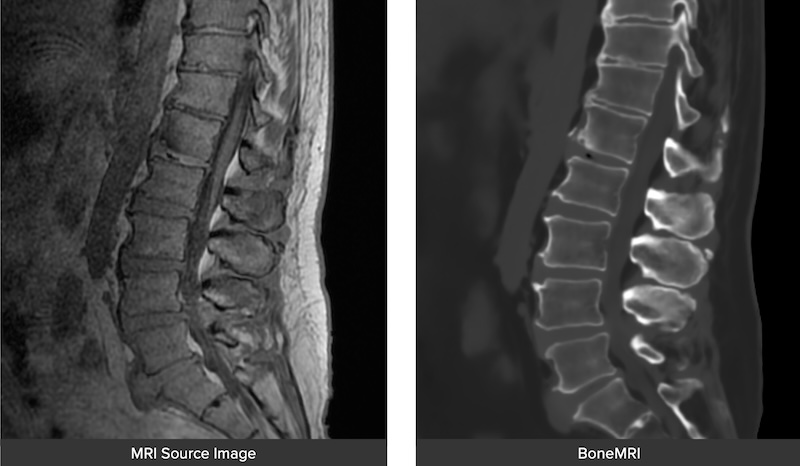

The Orthofix-SeaSpine 7D FLASH Navigation system is a comprehensive and flexible system that is imaging agnostic and provides several unique options for spinal and cranial navigation. The system utilizes Machine-vision that uses structured light and software to deliver registration in less than 30 second. It is utilized in cranial, spinal, percutaneous procedures. Also features MRIVision which is proprietary software that utilizes a special MRI sequence to render a synthetic CT from MRI making it possible to complete with no radiation.

• MRIVision Module:

• Utilizes a specialized MRI sequence acquired preoperatively to produce a synthetic CT image which can be used to perform intraoperative FLASH for instant registration.

• Makes a completely radiation free process